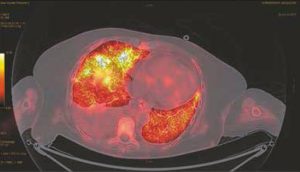

Qui est éligible aux traitements oncologiques après l’âge de 80 ans ? Entre considérations oncogériatriques et éthiques